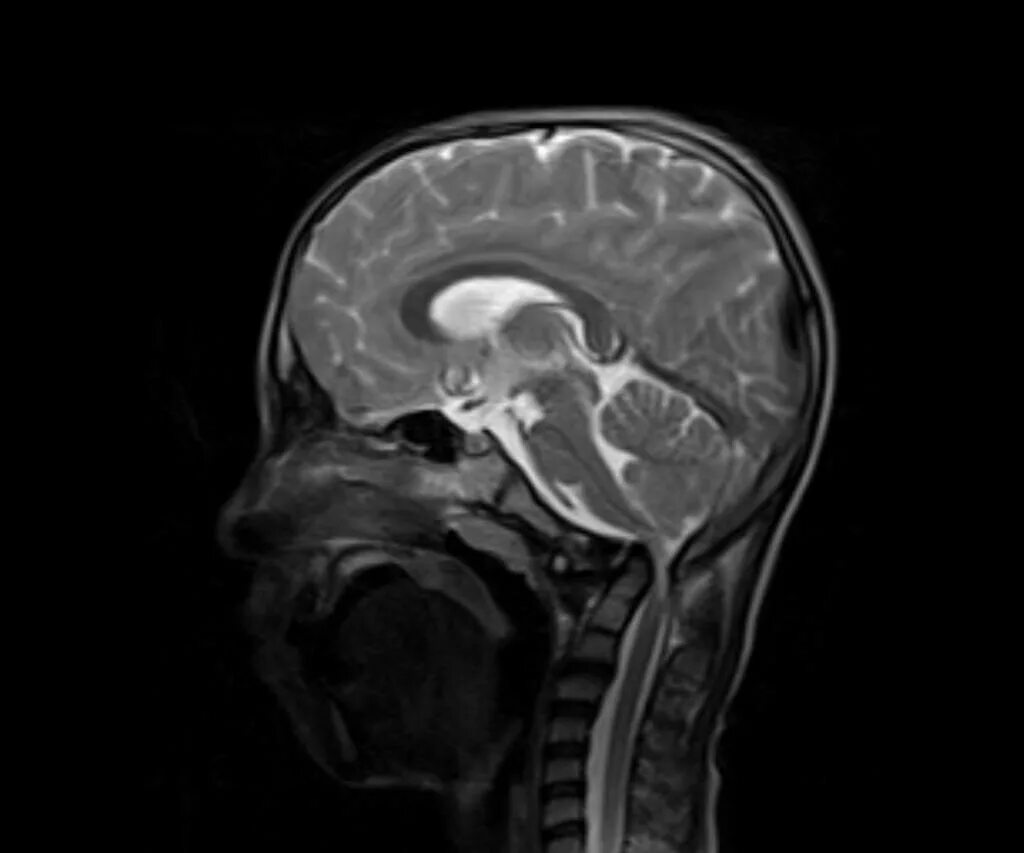

Аномалия перехода